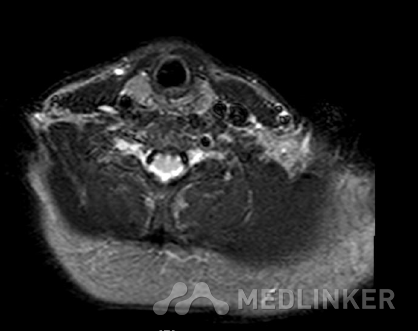

主诉:「发现枕颈部皮下肿物10年〕 病史:患者诉10年前发现右侧枕颈部皮下肿物,近1年增大明显,并伴有触摸痛,无红肿,无破溃。行MRI示右侧颈枕部皮下软组织包块并明显强化,性质待定。为求治疗来我院就诊,门诊以“枕颈部皮下肿 物”收入院。患者自入院,神志清,精神可,体重无明显改变,二便正常.

MR:(右枕颈部皮下)梭形细胞肿瘤,倾向为神经纤维瘤,建议做免疫组化辅助诊断。